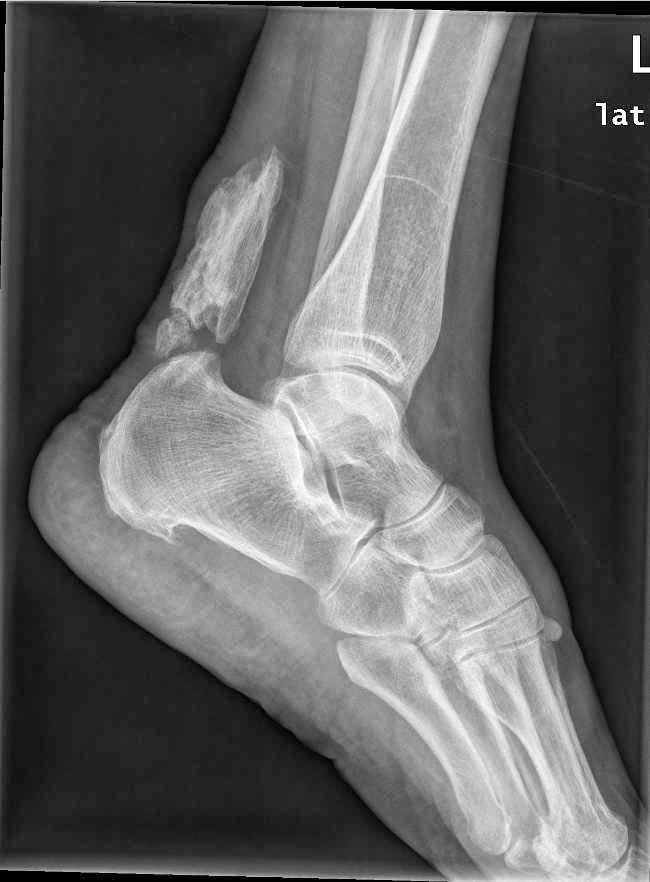

WebLas calcificaciones son muy frecuentes, aunque no siempre son la causa del dolor ya que a veces pueden provenir de la propia inflamación que genera esa calcificación. WebEl tendón de Aquiles o también llamado tendón calcáneo, es un tejido fuerte y resistente de la parte posterior e inferior del miembro inferior que sale de la unión de varios músculos. WebLas principales causas de las calcificaciones en el tendón de Aquiles son: “Una tendinitis/tendinopatia crónica mal curada, un sobreuso y microtraumatismos. WebEl tendón de Aquiles es el encargado de propulsarnos al caminar, correr o saltar. Los tendones son estructuras que unen el músculo al hueso, y el tendón de. WebLa tendinopatía calcificada insercional del tendón de Aquiles (ACIT) es una afección causada por el deterioro del tendón de Aquiles en el talón, que da lugar a. WebCALCIFICACIONES EN EL TENDÓN DE AQUILES. Prentamos el caso clínico de una paciente mujer de 53 años que acudió a nuestra consulta con dolor en el talón derecho. WebEn nuestro estudio hemos detectado radiológicamente (radiografía lateral de rodillas) calcificaciones de los tendones gastrocnemios en el 27,7% de las rodillas evaluadas, lo. WebTratamiento calcificación tendón de aquiles con ondas de choque. Hoy os mostramos un vídeo del tratamiento satisfactorio aplicado a un paciente con una.

WebEn nuestro estudio hemos detectado radiológicamente (radiografía lateral de rodillas) calcificaciones de los tendones gastrocnemios en el 27,7% de las rodillas evaluadas, lo. WebTratamiento calcificación tendón de aquiles con ondas de choque. Hoy os mostramos un vídeo del tratamiento satisfactorio aplicado a un paciente con una.